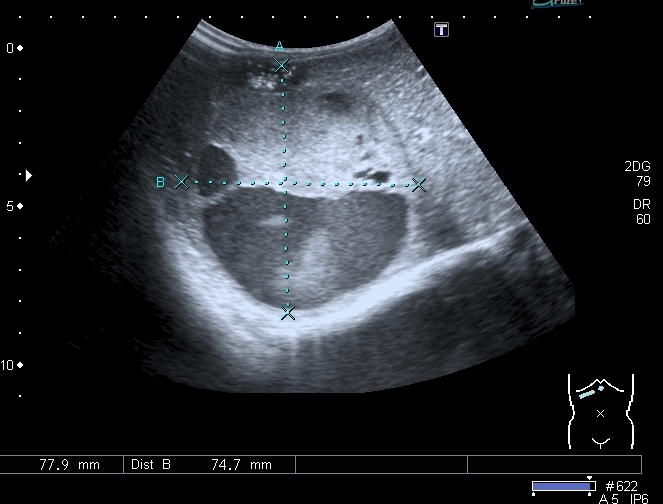

В хирургический приёмный покой поступил ребёнок 2-х лет с жалобами родителей на увеличение живота. Направлен на УЗИ с диагнозом "Опухоль Вильмса справа?"

При осмотре - живот увеличен в размерах, в правой половине пальпируется плотное образование.

При УЗИ вся правая половина живота выполнена солидно - кистозным образованием больших размеров.